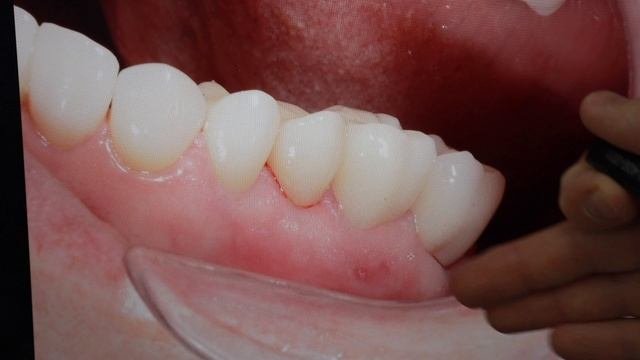

СТОМБУДНИ#18 ЧТО КУПИЛ НА ВЫСТАВКЕ_ #стоматология

Стомбудни#8.  ОТКУДА ДОСТАЛ ЗУБ_  ПЕРЕДЕЛЫВАЮ СВОЮ РАБОТУ

Стомбудни #6.  НИКОГДА ТАК НЕ ПРОТЕЗИРУЙ

СТОМБУДНИ#17  МАТЕРИАЛЫ! ЧЕМ РАБОТАЮ_ #стоматологическиематериалы